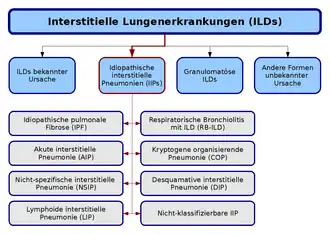

Classification

La classification des pneumopathies interstitielles diffuses idiopathiques se base sur une ligne définie en commun par l´American Thoracic Society (en) et l´European Respiratory Society (en), publiée en 2002. Selon cette classification, on distingue sept formes, qui se définissent par différents critères cliniques, radiologiques et pathologiques. Une huitième catégorie regroupe les formes non classifiables :

- Fibrose pulmonaire idiopathique

- Pneumonie interstitielle non spécifique

- Pneumonie à organisation cryptogène

- Pneumonie interstitielle aigüe

- Bronchiolite respiratoire avec maladie pulmonaire interstitielle

- Pneumonie interstitielle desquamative et

- Pneumonie interstitielle lymphoïde[2].

L'importance de cette nouvelle classification est avant tout la définition interdisciplinaire des diverses formes, qui précédemment, étaient généralement étudiées dans des publications indépendantes de pathologistes, de radiologues et d'internistes. Il a été clairement établi que l'on doit distinguer le type histopathologique du diagnostic clinique. Un diagnostic clinique sûr doit s'appuyer aussi bien sur des preuves cliniques, que radiologiques ou aussi histopathologiques. Certes, le degré d'évidence pour distinguer les classes est faible mais la classification fournit une bonne base pour des études futures, car elle donne des critères unifiés dans ce domaine[6].

UIP : pneumonie interstitielle usuelle — IPF : Fibrose pulmonaire idiopathique — AIP : Pneumonie interstitielle aigüe — NSIP : Pneumonie interstitielle non spécifique

DIP : Pneumonie interstitielle desquamative — RB-ILD : Bronchiolite respiratoire avec maladie pulmonaire interstitielle

BIP : Pneumonie interstitielle bronchiolitique — BOOP : Bronchiolite oblitérante avec pneumonie organisante — COP : Pneumonie interstitielle cryptogène

LIP : Pneumonie interstitielle lymphoïde — LPD : Maladies lymphoprolifératives

GIP : Pneumonie à cellules géantes — Hartmetallfibrose : Fibrose des métaux durs.